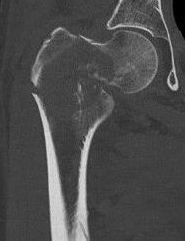

Femoral Neck pathological fracture / Major bone loss

Issues

- fracture unlikely to heal

- hemi versus THA

- long versus short stems